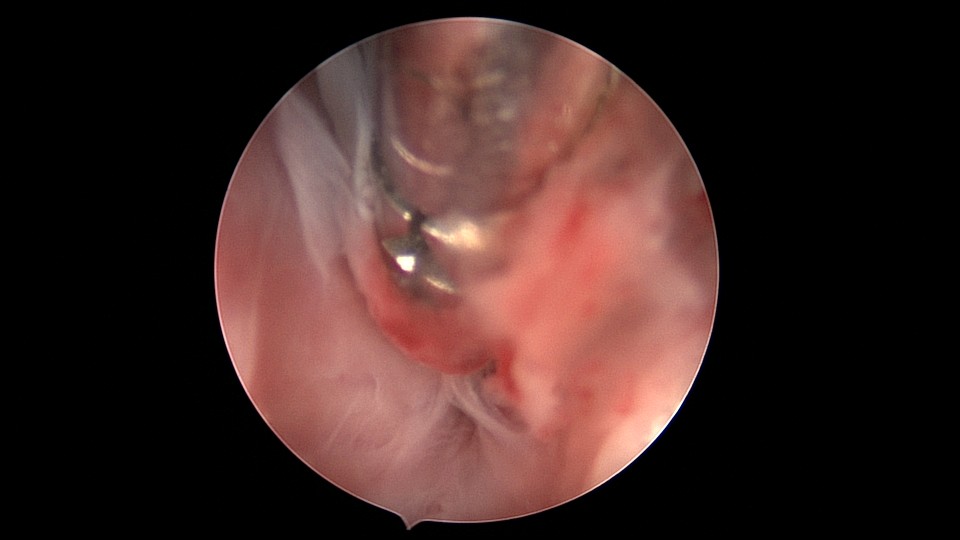

患者53岁,G3P1,剖宫产1次。安环13年,绝经8年,外院取环失败。患者阴道、宫颈及子宫萎缩,很难置入扩阴器,很难牵拉宫颈,宫颈外口位于前穹隆顶端,子宫极度前倾前屈位,且子宫与盆壁粘连,被拉长,宫腔镜很难进入,B超监护下异物钳扩张宫颈管上段及宫颈内口,宫腔镜艰难进入宫腔,见T型环两横臂嵌顿于两侧宫角,尾丝断裂,异物钳取出节育环,宫腔未见其他异常。